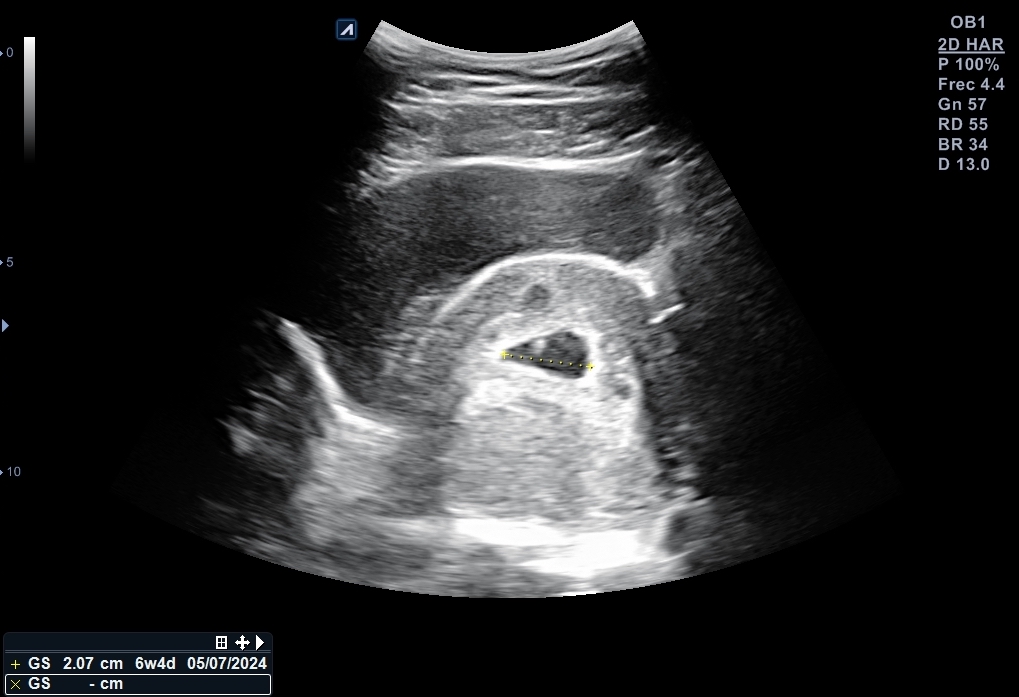

Se explora pelvis con sonda cónvex: vejiga distendida de paredes lisas y homogéneas. Útero en anteversión con endometrio decidualizado y saco embrionario en su interior, bien posicionado con una estimación de 6 + 2 semanas de gestación. Se localiza cuerpo lúteo en anejo izquierdo que, además está aumentado de tamaño.